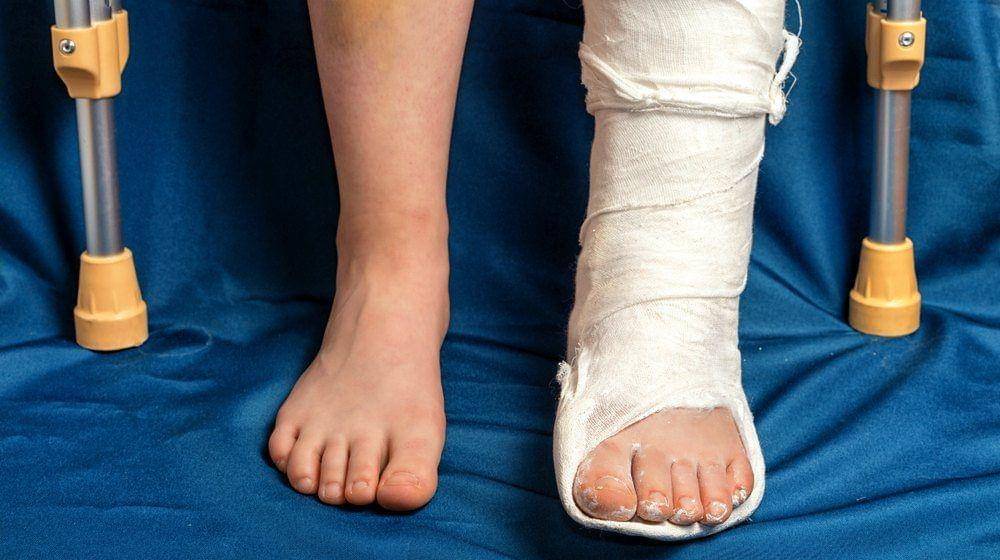

4. Patah tulang

Tergantung pada tingkat keparahan patah tulang dan seberapa baik seseorang mengikuti rekomendasi dokter mereka, tulang dapat memakan waktu antara mingguan hingga bulanan untuk sembuh. Menurut Klinik Cleveland, waktu penyembuhan tulang rata-rata adalah antara 6-8 minggu, meskipun bisa bervariasi tergantung pada jenis dan lokasi cidera.